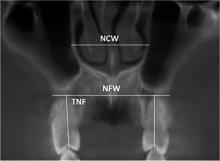

Objective To analyze the clinical outcome of microimplant screw-assisted maxillary rapid arch expansion in patients with Class Ⅲ malocclusion. Methods A total of 58 patients with Class Ⅲ malocclusion treated at Handan Stomatological Hospital from January 2022 to April 2023 were selected as the control group, and surgically assisted rapid maxillary arch expansion treatment was used. A total of 58 patients with Class Ⅲ malocclusion treated at Handan Stomatological Hospital from June 2023 to May 2024 were selected as the observation group, and micro-implant assisted rapid maxillary arch expansion treatment was performed. After 3 months of treatment, cone beam CT was taken to compare the bone structure, soft tissue measurement results, occlusal function, arch expansion effect, and postoperative complications between the two groups of patients before and after treatment. Results The bony width and the tilt of the supported teeth of the maxillary teeth increased in both groups after treatment, compared with the preoperative period(P<0.05). The nasal width of the maxillary first molar in the observation group increased significantly, and the tilt of the supported teeth were all reduced significantly compared with the control group(P<0.05). After treatment, ANB and LI-MP of the observation group were higher than those of the control group; SNB and MP-SN were lower than those of the control group. Facial convexity angle and nasolabial angle were higher than those of the control group; chin-labial angle was lower than those of the control group, and occlusal function was higher than those of the control group(P<0.05). The postoperative complication rate of 1.72% in the observation group was lower than that of 13.79% in the control group, with a significant difference(P<0.05). Conclusion Micro-implant-assisted rapid maxillary arch expansion can achieve obvious bony expansion effect, promote the improvement of the patient’s bony structure, improve their facial morphology, and enhance their occlusal function, which can be promoted and applied.